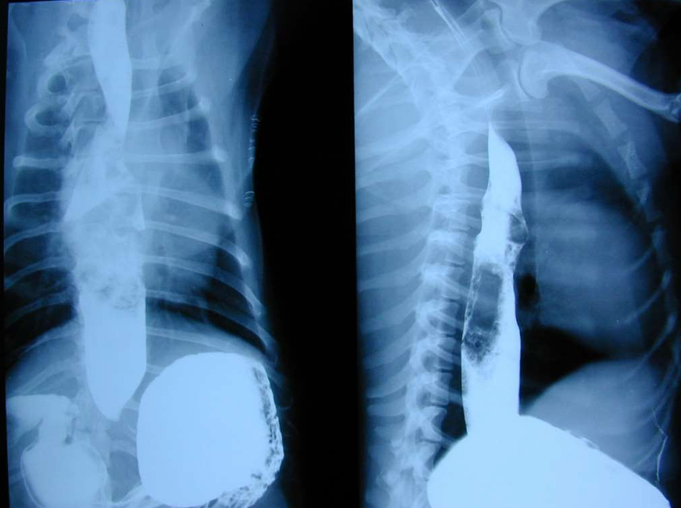

![]() | OHE 수술 1주일 후 발생한 regurgitation 조영제가 식도 통과하지 못하고 막힘. |